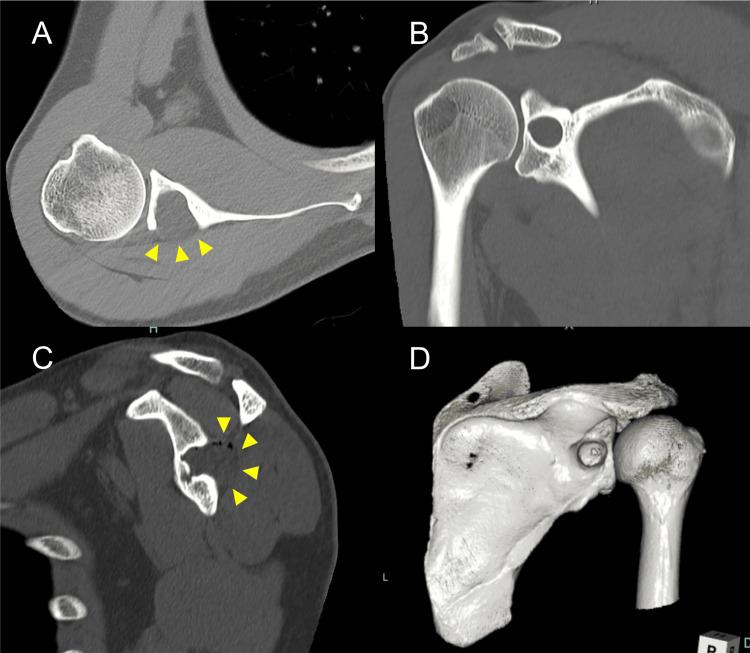

Suprascapular nerve entrapment caused by intraosseous cystic lesions is a rare condition. We present the case of a 49-year-old man with right shoulder numbness, slight infraspinatus (ISP) weakness, and shoulder pain. He underwent open surgery and arthroscopic evaluation. The cystic lesion, histologically diagnosed as a ganglion, was resected, and the bony defect was filled with artificial bone. Immediately after the operation, the shoulder numbness and muscle weakness resolved. At the one-year follow-up, the patient's right shoulder pain disappeared, and he had excellent clinical results. An intraosseous cyst protruding into the spinoglenoid notch, causing suprascapular nerve entrapment, might elicit neurological symptoms and glenoid fracture. However, the treatment and clinical course of this condition are still unknown. This case suggests that patients treated with tumor resection and bone grafting to the bony defect in this abnormality may have favorable outcomes.

骨内囊性病变导致的肩胛上神经卡压是一种罕见疾病。我们报告一例49岁男性患者,其出现右肩部麻木、冈下肌(ISP)轻度无力及肩部疼痛。他接受了开放手术及关节镜评估。组织学诊断为腱鞘囊肿的囊性病变被切除,骨缺损用人工骨填充。术后肩部麻木和肌肉无力立即缓解。在一年的随访中,患者右肩部疼痛消失,临床效果极佳。一个向肩胛下切迹突出并导致肩胛上神经卡压的骨内囊肿可能引发神经症状和关节盂骨折。然而,这种疾病的治疗方法和临床过程仍不明确。该病例表明,针对这种异常情况采用肿瘤切除及骨缺损植骨治疗的患者可能会有良好的预后。